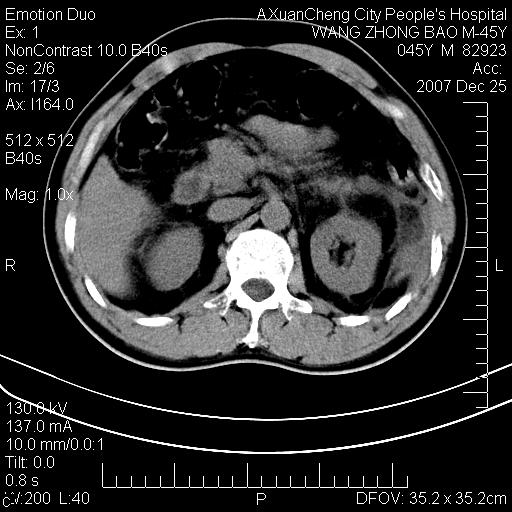

以下是引用qiuleiyu在2007-12-25 18:14:00的发言:[br]胰腺增大,周边渗出改变,肾前筋膜明显增厚,示少量积液.胆囊壁毛糙,周边少许渗出,胆总管壁厚,异常强化,然扩张不明显.结合病程急短;考虑;胆管炎,胆囊炎,胆源性胰腺炎可能大,请结合实验室检查及随访.

以下是引用lisihao在2007-12-25 14:23:00的发言:[br]急性水肿型胰腺炎[br]依据:1、胰腺弥漫性肿大,边缘稍毛糙;[br] 2、双侧肾周筋膜增厚,尤以左侧为甚(重要征象)[br] 3、双侧后胸膜增厚(刺激性炎症);[br] 4、结合病史,查血尿淀粉酶应该可以确诊。